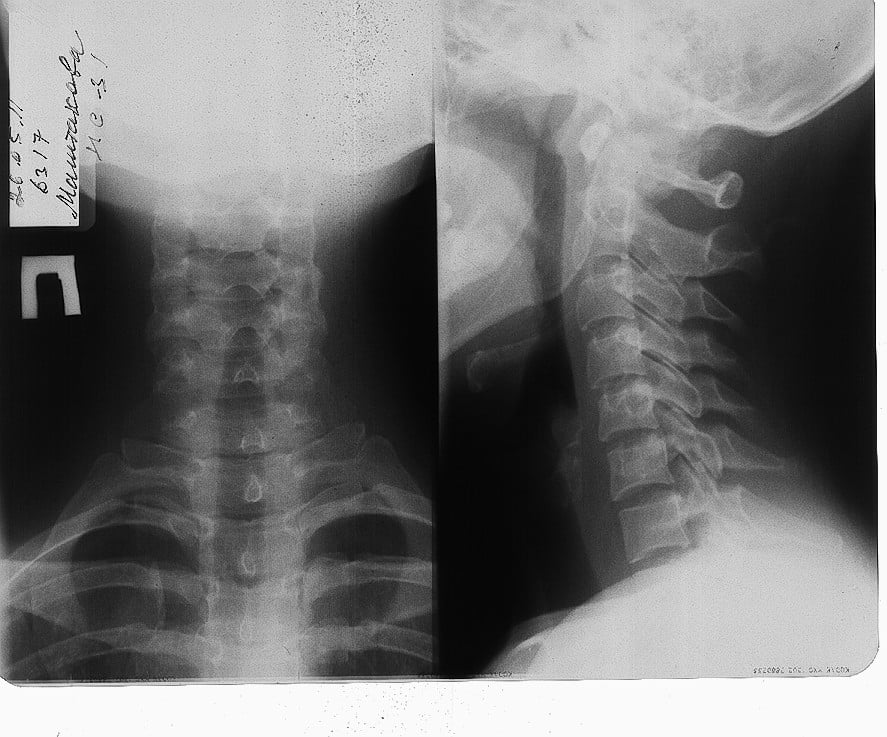

Медицинские снимки: рентген позвоночника сбоку